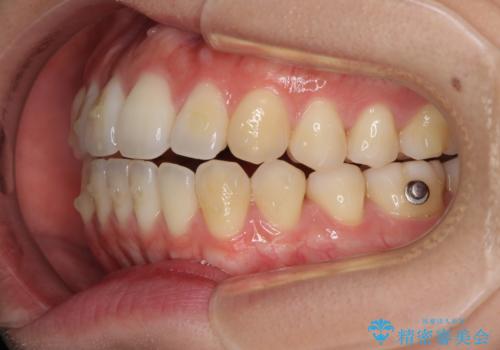

オープンバイトでかみにくい インビザラインによる矯正治療

- 前歯の上下スペースによる食べにくさを気にして来院された患者様です。

インビザラインにより上下の前歯の隙間を閉じていくこととしました。

上下の奥歯を圧下させるようにすることで、前歯を接触させるように計画しました。

上下の隙間に舌が入り込むことがオープンバイトの原因であったため、舌の筋肉のトレーニングも並行して行い、後戻りの抑制を図りました。